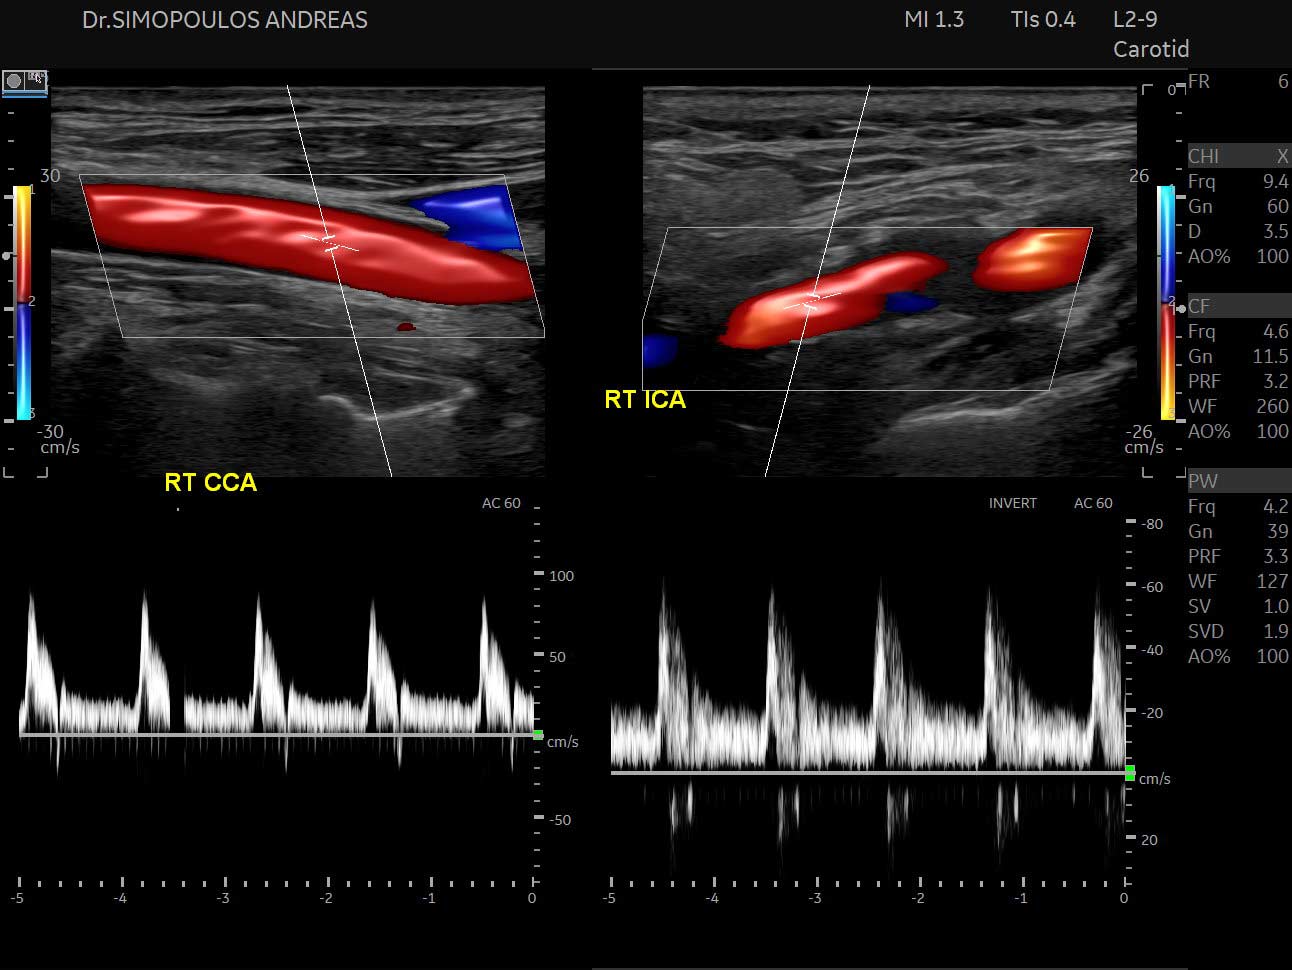

Triplex Αγγείων

- Καρωτίδων και σπονδυλικών αρτηριών